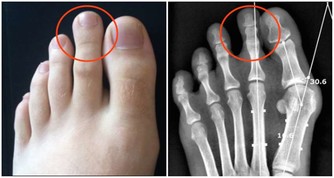

3、指甲呈扁圓型

有時候指甲的形狀會出現2種改變方式,一種是指甲呈現扁圓狀改變,另一種則呈現半圓形改變。如果你的指甲扁圓形改變,說明你的腸味淤積的毒素過多,可能還伴有慢性腸炎、消化不良等腸胃疾病。一般此類病人還會有營養代謝障礙,這樣一來就會影響其他臟器的正常運行,特別是對肺部的影響較大。